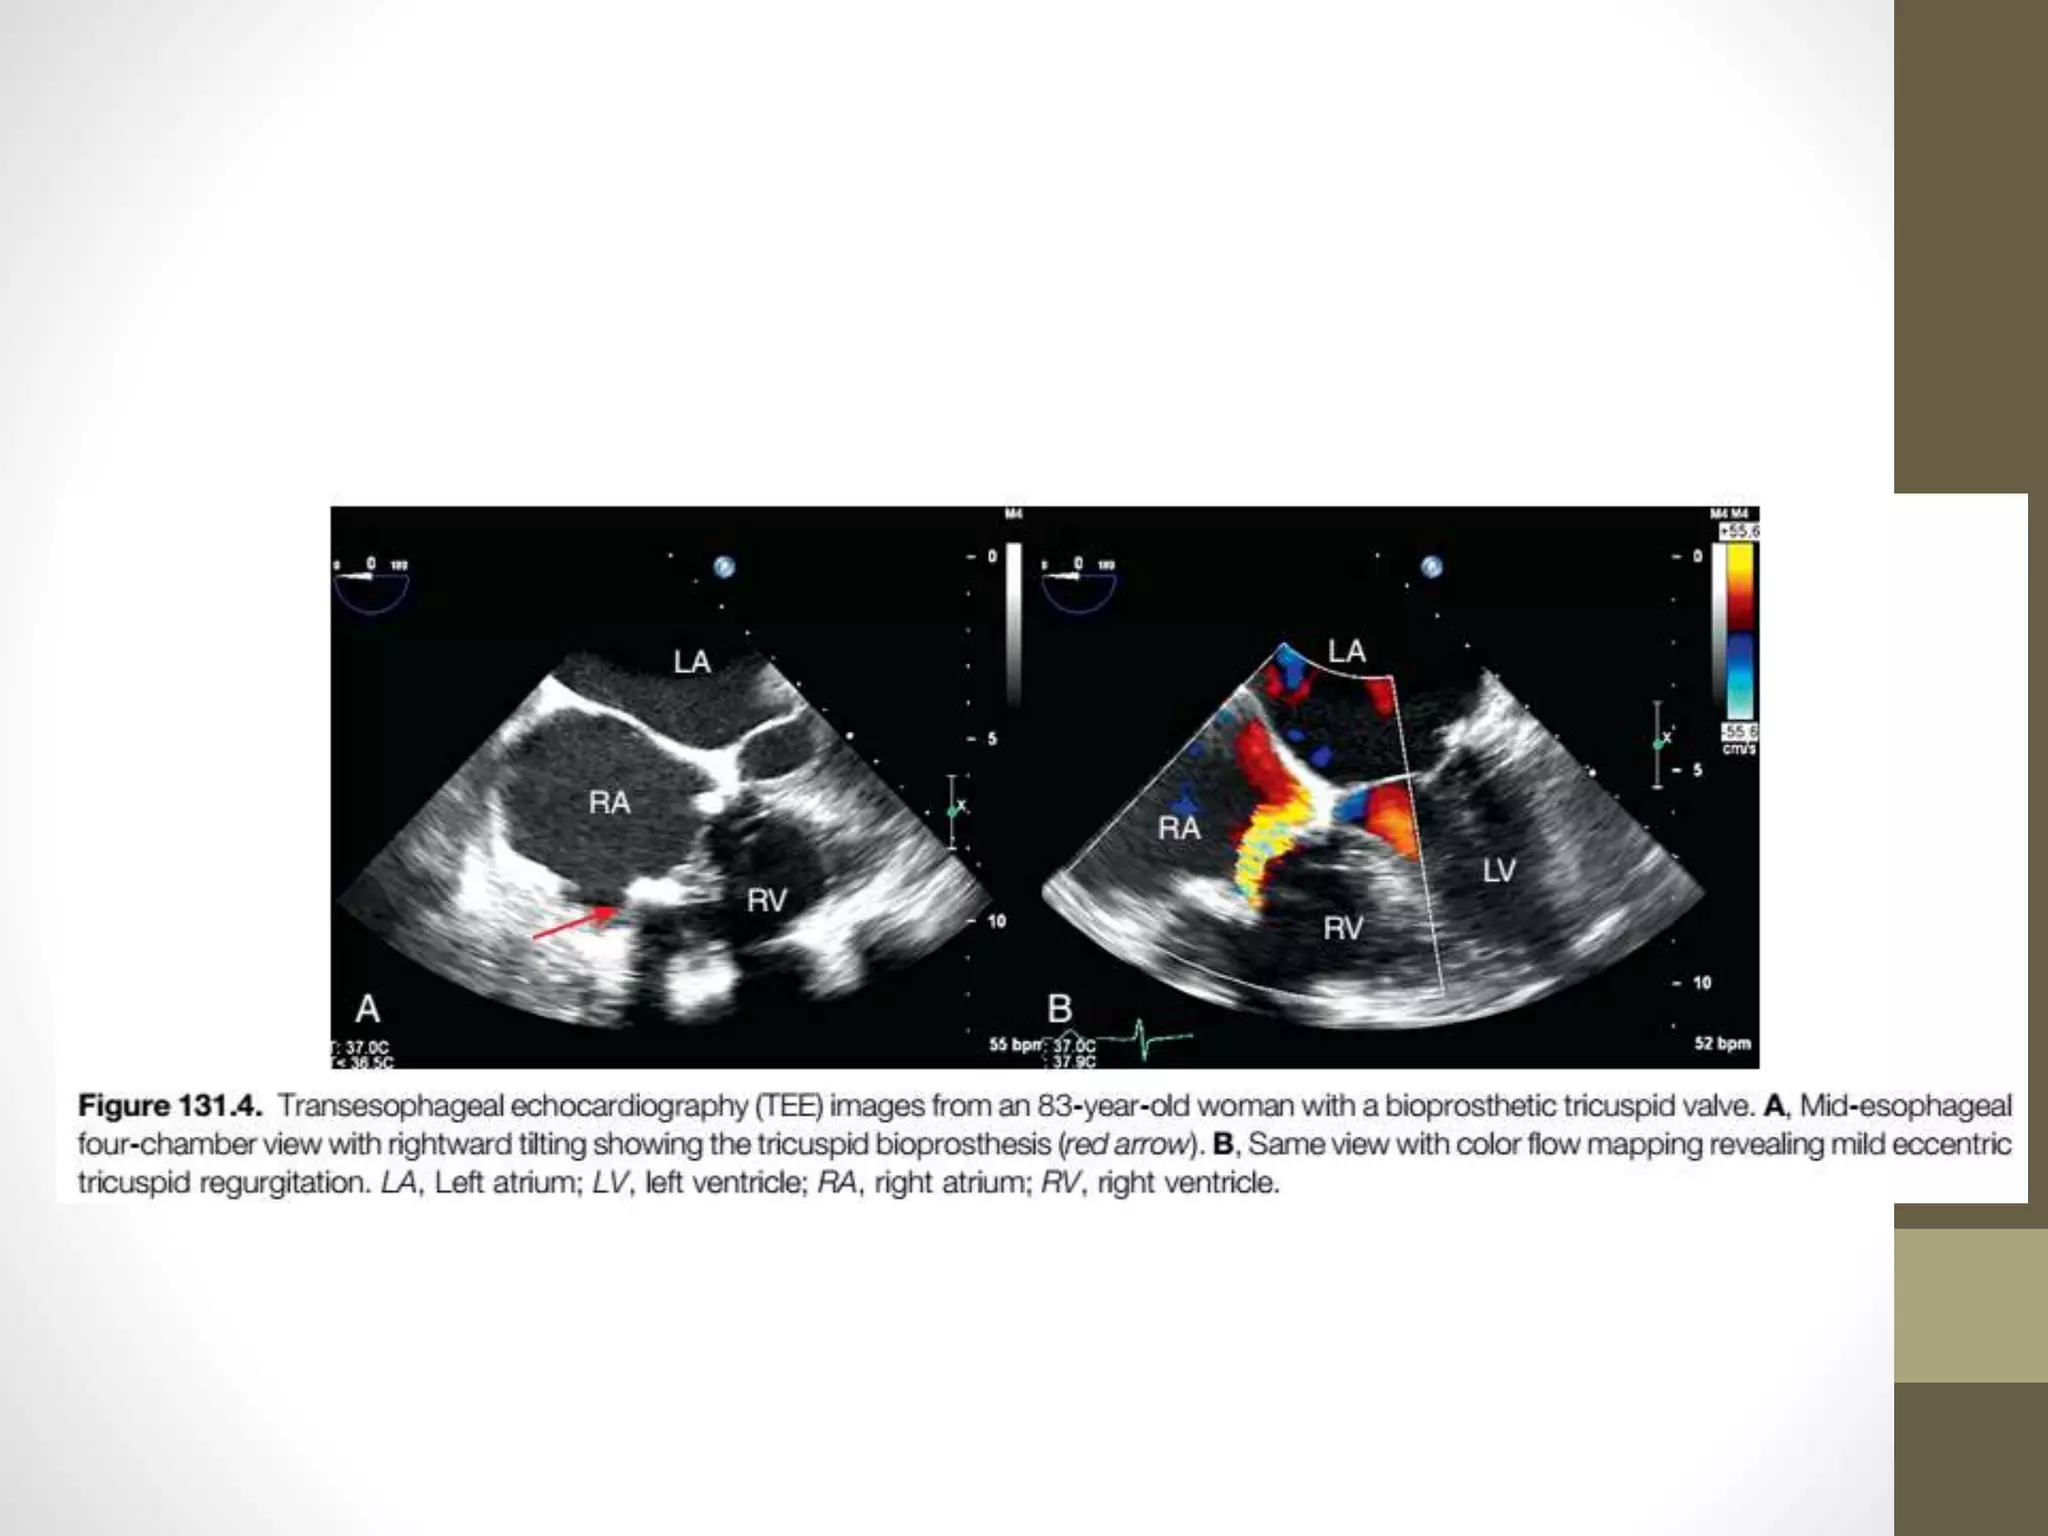

TransesophagealEchocardiographyInPatientsWith

ProstheticTricuspidValves

• TEE is indicated for the evaluation of patients with the

possible diagnosis of prosthetic valve endocarditis or

valvular thrombosis, including reevaluation when a change in

therapy is anticipated.

• TEE is the modality of choice for guidance of transcatheter

procedures and whenever TTE is nondiagnostic.